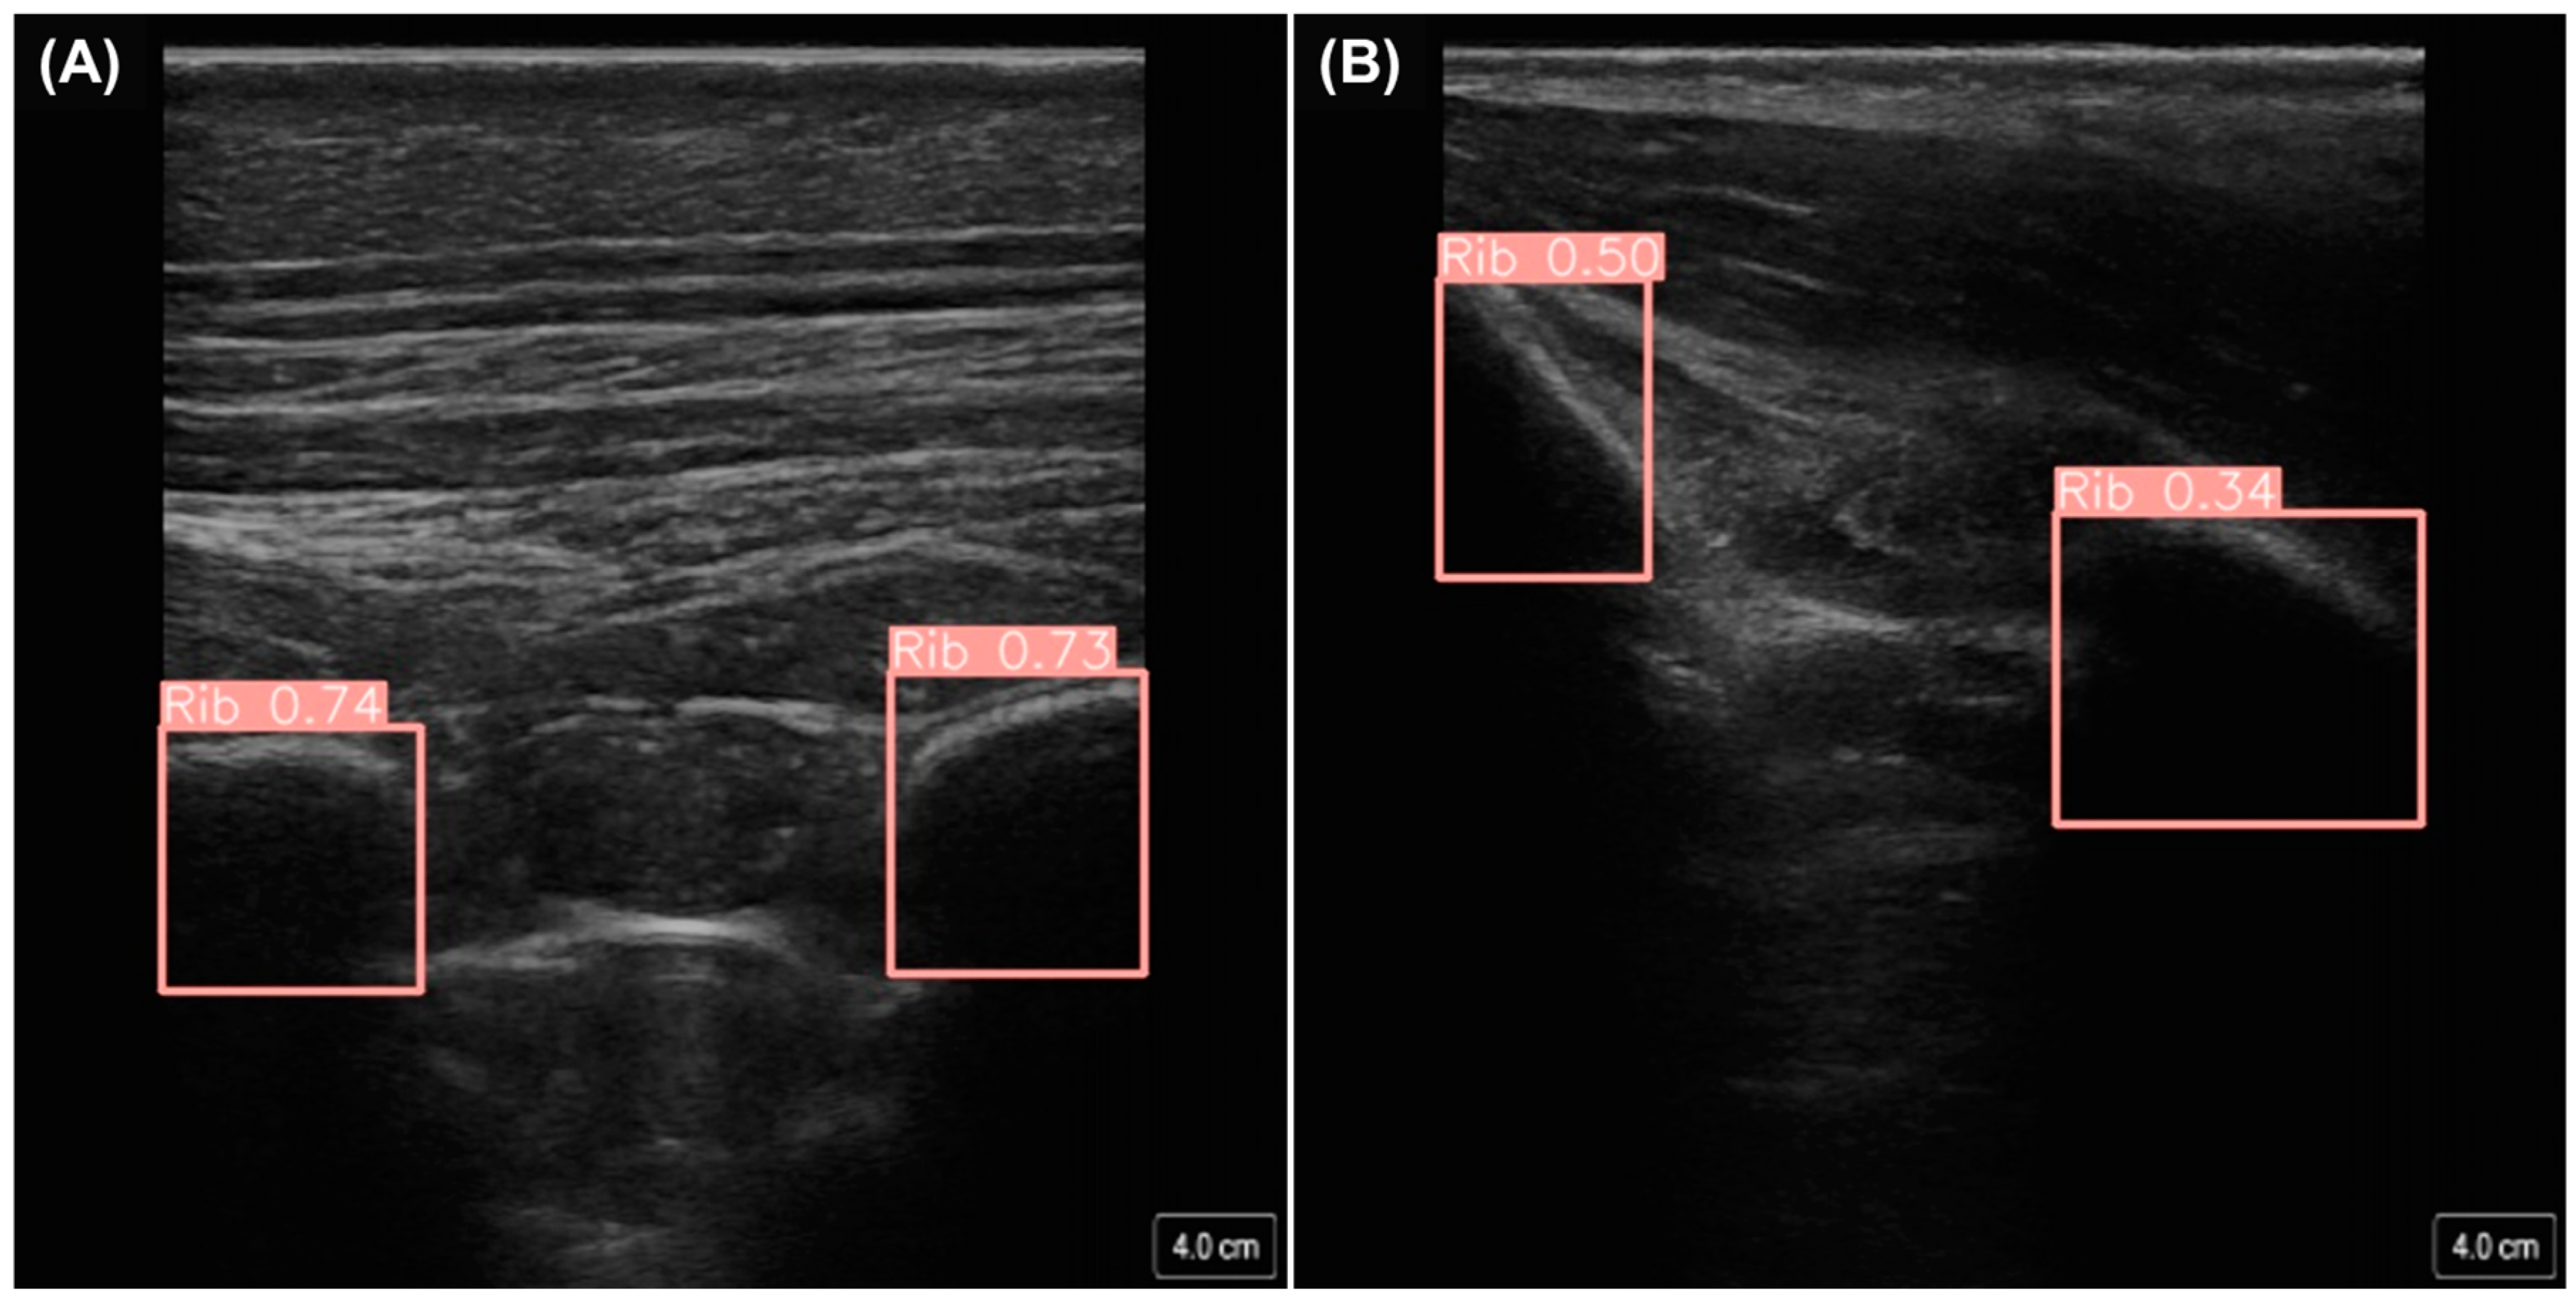

For the development of diagnostic models focused on the thoracic region, we first generated M-mode images from the original B-mode US scans. This approach used a sequence of consecutive frames to create custom M-mode images. Each frame was processed through the guidance model for rib detection and, based on the predicted rib locations, the central point between the ribs was calculated. At this central point, a vertical slice was extracted from each frame (Figure 4). These slices were then concatenated to generate an image that closely resembled a genuine M-mode image. To ensure that a generated M-mode image was indicative of its diagnosis, the rib detection guidance model was used to filter out images without only two ribs visible. If a frame did not have exactly two ribs detected, that set of subsequent frames was not used for the M-mode creation process.

Figure 4.

Overview of how M-mode images were generated from B-mode frames using rib guidance AI models. Shown first is a traditional B-mode ultrasound frame from which the guidance AI determined the location of the ribs (blue bounding boxes). A 3-pixel-wide region at the midpoint between the bound boxes (red dotted region) is selected across each frame to create a custom M-mode image (shown on the right).